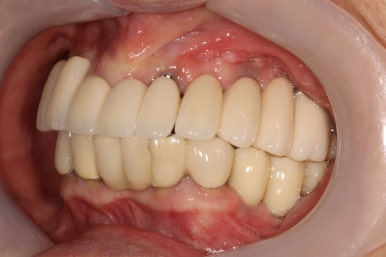

앞에서 볼 땐 많이 테가 안날수도 있겠지만...

어금니 우측

좌우측 측면 사진 비교시, 아래 어금니 임플란트로 깔끔하게 메꿔진 빈 공간이 인상적입니다!